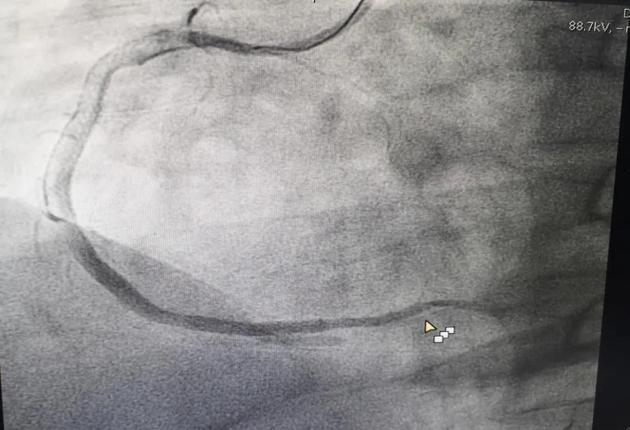

心脏介入手术持续了差不多一个小时,从M老师一根堵塞的血管中抽出了大量新鲜血栓,并在严重狭窄的部位植入了两枚支架,整个血管恢复了良好的血流。

血管开通后